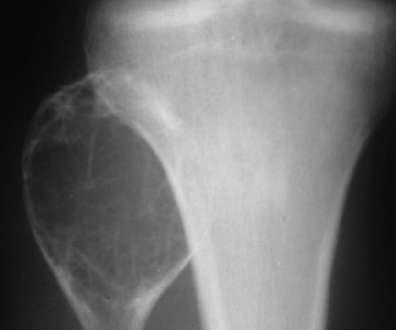

临床与病理:1、年龄:20-40岁,约65%;2、部位:长管状骨骨端,膝关节附近居多

X线表现:① 多数为偏心性骨破坏 (溶骨型)② 局部骨 膨胀性,骨皮质变薄形成薄层骨壳,无硬化边③ 大小不一的分隔小房呈肥皂泡状, 并见骨嵴。

④ 无骨膜反应,⑤一般不穿破关节软骨

桡骨远端偏侧性膨胀性骨质破坏,中有骨嵴。